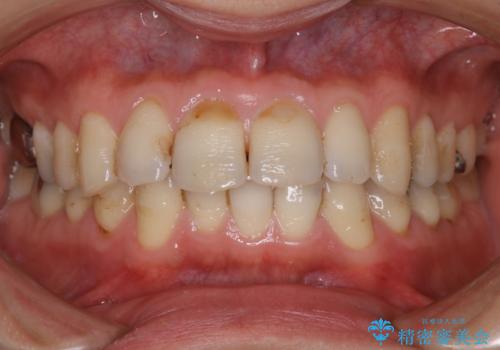

歯の表面に、茶色く色が残っている所がありますが、これは詰め物の変色の所と、虫歯になっている所です。以前に、CR(コンポジットレジン)による虫歯治療がされています。

CRは経年的劣化や、着色してしまうことがあります。PMTCでクリーニングを行うと、古いCRが目立つことがあるため、気になる際は詰め替えを行います。

茶色くなっている部分が、着色なのか、劣化なのか、虫歯によるものなのかは判別が難しいことがあります。そのため、定期的にPMTCを行うことで状態の確認が的確に行えます。

また、治療が開始される前などにも、全体的にクリーニングを行いご自身本来の歯の色、状態を精密に確認することが大切です。